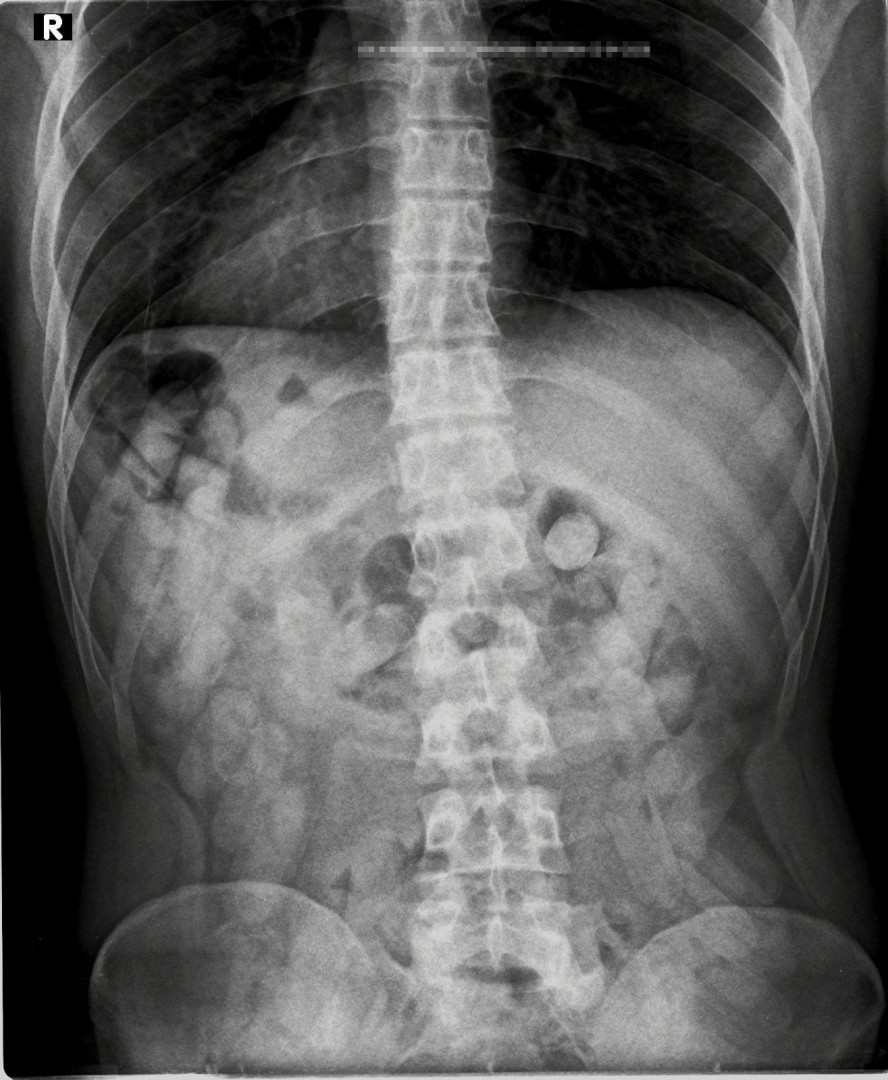

Durante la inspección, cuatro pasajeros de nacionalidad boliviana, debido a fuertes dolores estomacales, manifestaron haber ingerido dosis de estupefaciente. Entendiendo que la modalidad "mulas" o "cápsuleros" es altamente peligrosa para la salud, se trasladó a los involucrados al Centro de Salud Zenón J. Santillán ubicado en la ciudad de Tucumán, donde les realizaron las placas radiográficas y pudieron observar la presencia de cuerpos extraños en la zona del abdomen.

Finalmente, ayer, los involucrados expulsaron la totalidad de las cápsulas, contabilizando un total de 367 dosis. Los envoltorios fueron sometidos a la prueba de campo Narcotest, la cuál arrojó resultado positivo para cocaína con un peso de 4 kilos 403 gramos.